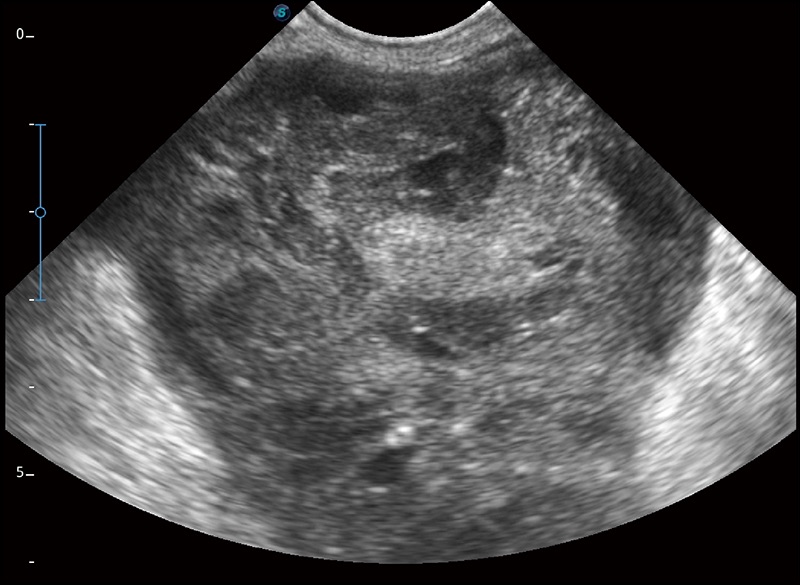

α1卓越的图像质量和便捷的工作流程,使每位宠物医生都能轻松扫查。其全面的兽用应用功能和紧凑型的结构设计,可以满足动物检查的多种需要。专业的预设检查模式和多领域测量软件包有助于为不同类型的动物提供检查, 让宠物医生能够出色的完成工作。

可实时观察感兴趣区域和病变位置